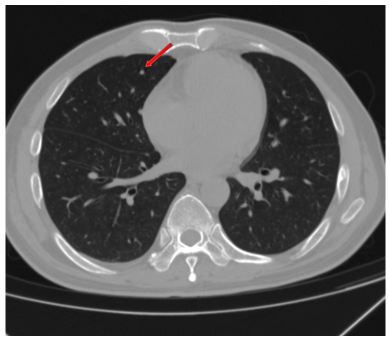

CEA、CA19-9略微升高(图17),肝脏多发转移瘤较前增多、增大(图15/16),双肺结节较前增多、增大(图14),评估为PD。

图14. 2025年2月25日CT:双肺结节,较2024年12月27日CT增多、增大